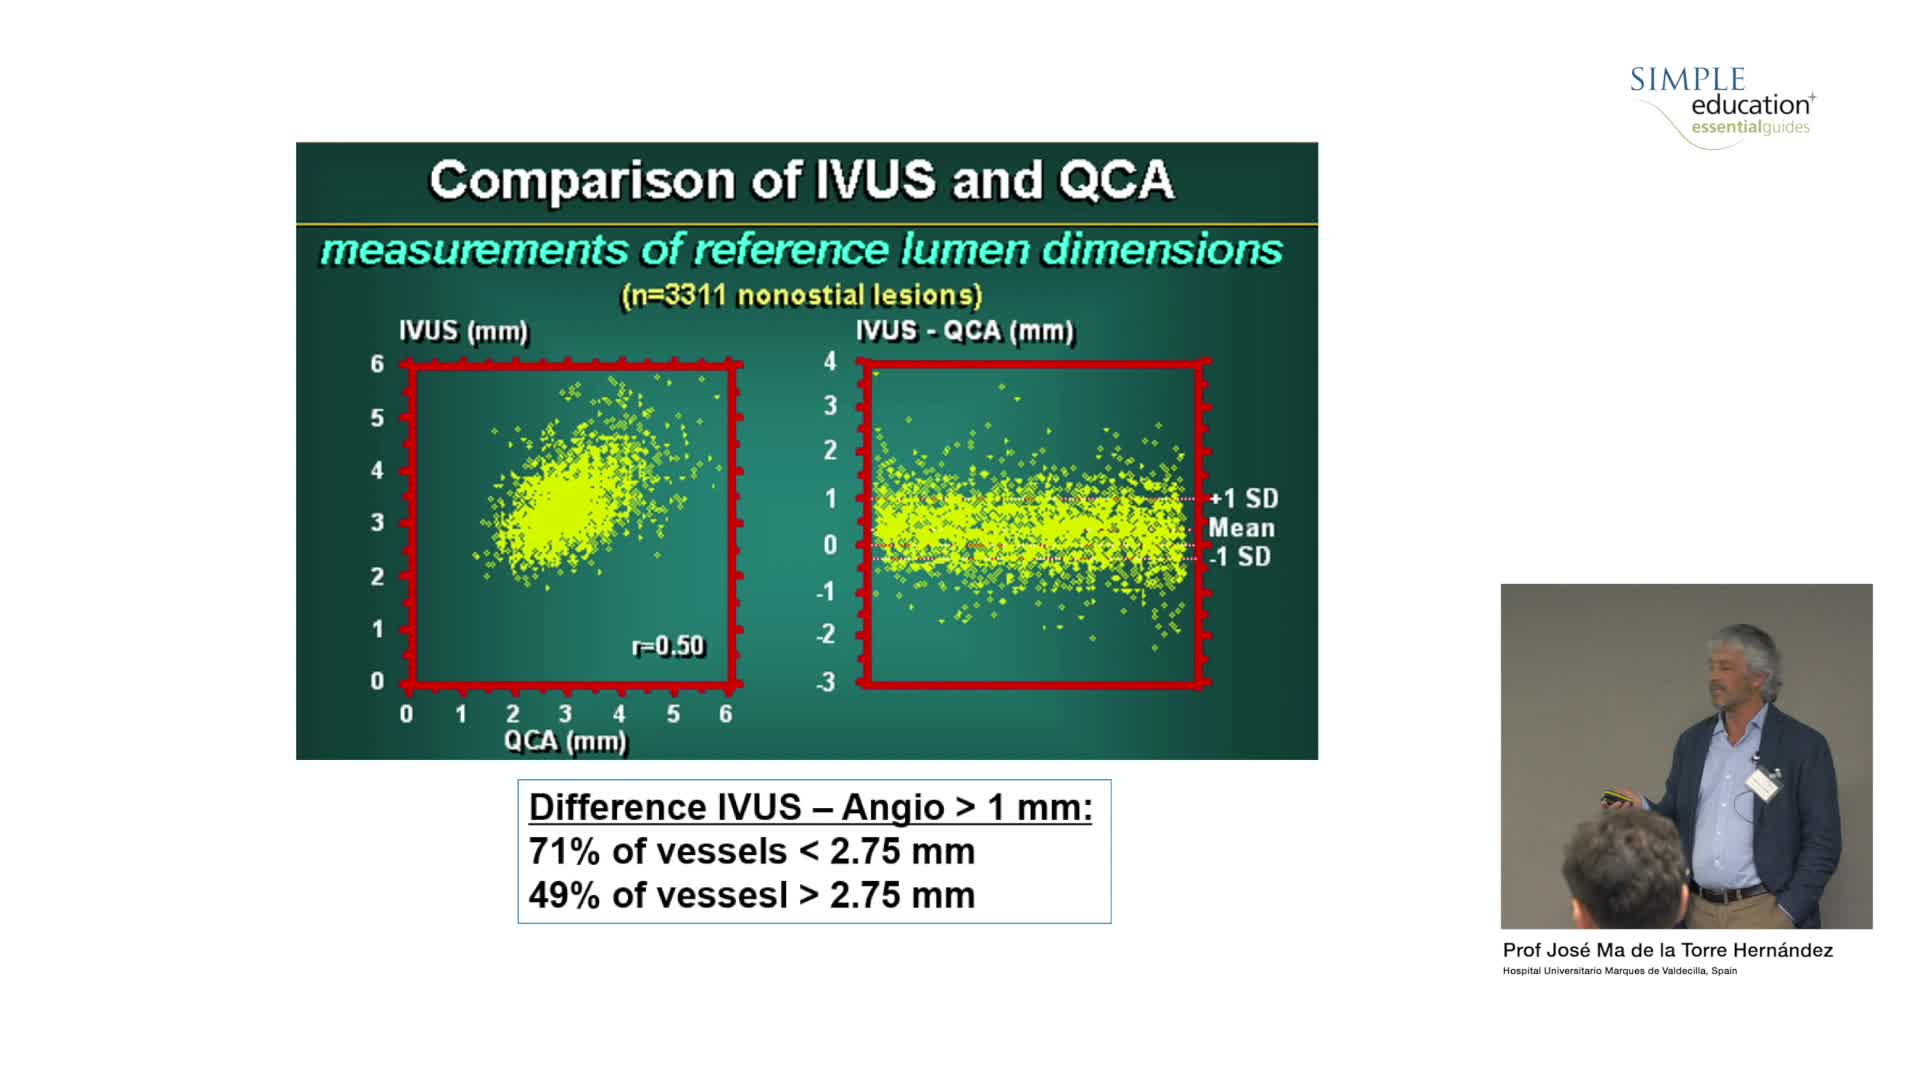

How to perform good co-registration measurements using iFR and IVUS - Prof Carlo Di Mario

Using SyncVision Co-registration to distinguish between focal and diffuse coronary disease. - Prof Giuseppe Tarantini

Essential Guide to Intra-coronary Imaging for the General Cardiologist - Dr. Iqbal Malik